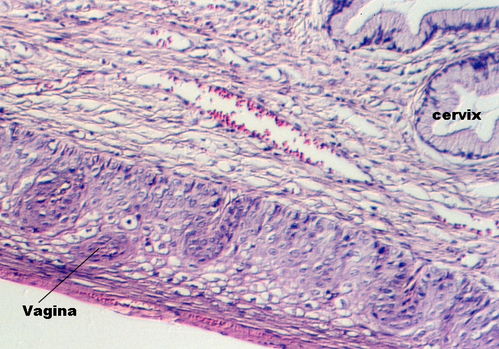

The uterus communicates with the outside world via a short canal called the cervix. The following photograph shows the uterus in the proliferative stage. The glands continue into the cervix in the left side of the photo.

The cervix continues and joins with the vagina. The cervix is lined by simple high columnar epithelium which consists of mucous cells. These are shown in the following views. In the lowest magnification, one can see bundles of smooth muscle in the wall (see below)

Moving toward the vagina, one can see the abrupt transition between the cervical glands and the stratified squamous epithelium of the vagina. The region showing the vaginal and cervical areas juxtaposed is seen in the following photo.